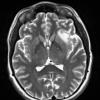

NEOPLASMS (GLIAL)

Astrocytoma, IDH-mutant, WHO Grade 2 (8)